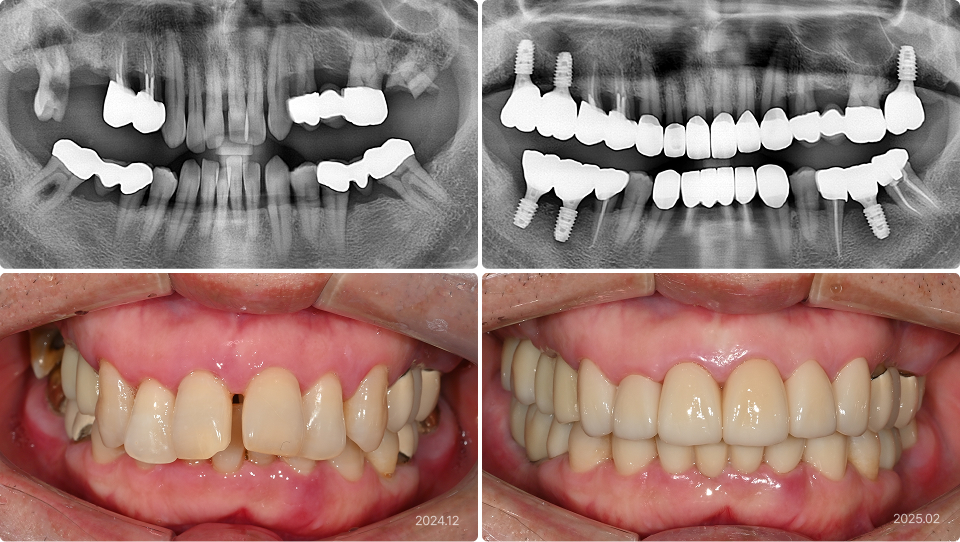

치료 기간을 단축하고 싶은 경우

“안 아프게, 최대한 빨리 치료를 마무리하고 싶어요.”

치료 전

치료 후

치료 내용

• 직장 사정으로 긴 치료기간과 잦은 내원이 불가하여 방치된 치아

• 의식하진정법(수면마취)으로 네 군데의 임플란트 수술, 전체 앞니 심미 보철 시행

• 힘든 진료를 모아서 시행하였고, 임플란트도 3개월만에 최종 완성